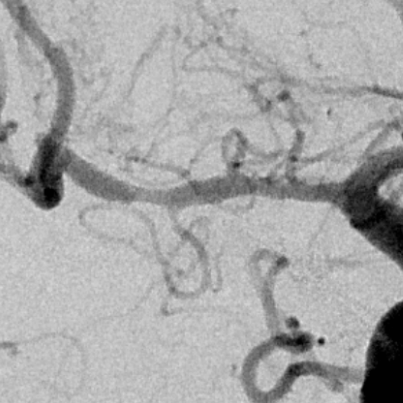

术后1.5个月随访

血管不错

血管进一步改善,继续保守治疗随访

支架进一步打开,直径改善到2.9mm

进一步打开的支架的形态,打开满意